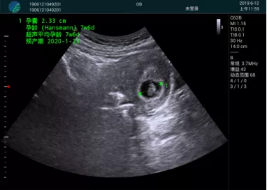

清晰顯示孕囊,通過(guò)軟件包計(jì)算孕齡7w+6d

M20實(shí)時(shí)引導(dǎo),術(shù)中清晰顯示孕囊被破壞和抽吸針的過(guò)程,清晰顯示吸引針

抽吸結(jié)束后縱切子宮,孕囊已被完全抽吸,未見(jiàn)明顯殘留

橫切子宮,發(fā)現(xiàn)右側(cè)宮腔靠近宮角處有少許脫模樣殘留

M20引導(dǎo)下,抽吸針找到右側(cè)宮角處再次清掃

二次抽吸后再次進(jìn)行超聲檢查,宮腔未見(jiàn)殘留,宮腔線清晰顯示